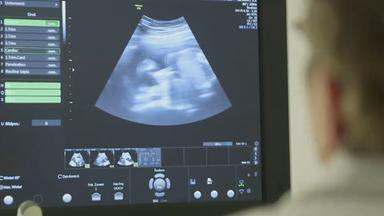

In Politik und Gesellschaft wird über den pränatalen Bluttest NIPT diskutiert, mit dem sich ein Trisomie-Test erkennen lässt. Was sagen Eltern und Mediziner?